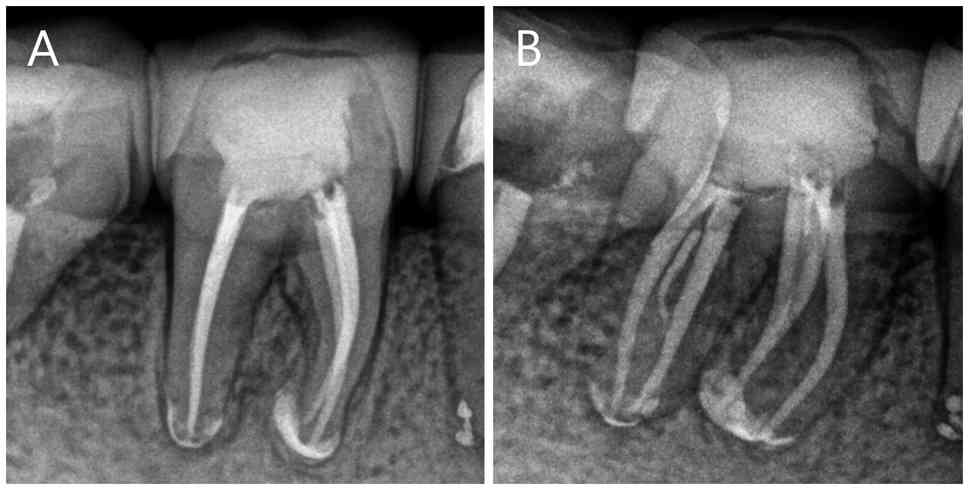

(November 2023). (A) Preoperative apical radiographs of teeth nos.

45 and 46. (B) Rubber dam isolation of teeth nos. 45 and 46. Dental

microscopic observation of three (C) mesial and (D) distal root

canal orifices of tooth no. 46 following preparation. ML,

mesiolingual; MM, Middle Mesial; MB, Mesiobuccal; DL, Distolingual;

MD, Middle Distal; DB, Distobuccal.

Figure 1

Clinical and radiographic assessment (November 2023). (A) Preoperative apical radiographs of teeth nos. 45 and 46. (B) Rubber dam isolation of teeth nos. 45 and 46. Dental microscopic observation of three (C) mesial and (D) distal root canal orifices of tooth no. 46 following preparation. ML, mesiolingual; MM, Middle Mesial; MB, Mesiobuccal; DL, Distolingual; MD, Middle Distal; DB, Distobuccal.

A 40-year-old Chinese female patient with no notable medical history presented to The Third People's Hospital of Chengdu (Chengdu, China) in November 2023 with chief complaints of pain in the lower right molar during mastication, persisting for 2 months. Additionally, the patient reported that the restoration on the same tooth had fractured 1 day earlier. The patient also recalled having undergone ‘endodontic treatment’ (July 2008) at the People's Hospital of Wenjiang District (Sichuan, China). This previous therapy involved partial pulp removal and mummification therapy on teeth nos. 45 and 46, followed by bridge restorations, which progressively deteriorated. Clinical examination revealed a notable fistula tract on the soft tissue surrounding tooth no. 46, which elicited slight pain and discharged pus upon palpation. The probing depth of the gingival sulcus was normal at all points except for the buccal intermediate of tooth no. 46, where a localized periodontal pocket measuring 7 mm was noted. Following the removal of the crown, tooth no. 46 displayed grade 1 mobility according to Miller's mobility index (21). Vertical percussion on the affected teeth caused noticeable pain and pulpal electro-vitality tests yielded no response. Periapical X-rays indicated high-density images in the crowns of teeth nos. 45 and 46, extending into the pulp cavity, with indistinct root canal images suggesting the presence of calcified canals. Additionally, diffuse radiolucent areas were observed in the apical regions of both teeth and the periodontal ligament space surrounding the cervical third and root bifurcation was widened (Fig. 1A). A dental cone-beam CT (CBCT) scan was recommended to improve understanding of the severity of the disease and the morphology of the root canal system. However, the patient declined this examination. Based on the clinical examination and radiographic findings, tooth no. 46 was diagnosed with chronic apical periodontitis. After being fully informed about their condition, the patient was given the option of non-surgical endodontic treatment or implant placement following extractions, with additional periodontal therapy potentially required. The patient opted for endodontic retreatment. Before beginning the treatment, the patient provided informed consent for all diagnostic and therapeutic procedures. Additionally, the Ethics Review Board of Chengdu Third People's Hospital (Sichuan, China) granted approval for the present report (approval no. 2025-S-83).

The first root canal treatment was performed in November 2023. Following removal of the defective restorations, teeth nos. 45 and 46 were isolated with a rubber dam (Fig. 1B). The previous filling material and secondary caries were removed and the pulp mummification materials within the pulp chamber were accessed. Furthermore, an endodontic ultrasound ET20 tip compatible with the Suprasson P5 Newtron device (both Acteon; Satelec), was employed to clear the pulp cavity of calcified and necrotic tissue. Subsequently, marked calcification was noted on the chamber floor, which appeared light brown and complicated the identification of the root canal orifices. With the aid of a dental operating microscope (DOM; Zumax Medical Co., Ltd.), a DG-16 endodontic explorer (Hu-Friedy) was used to probe the root canal orifices and the orifices of the mesiobuccal (MB), mesiolingual (ML), distobuccal (DB) and distolingual (DL) canals were initially detected. The wide separation of the MB and ML orifices raised suspicions of additional root canals. An ET25 ultrasonic tip (Acteon) was used to remove the calcified tissue in the isthmus between these orifices. The ‘champagne bubble test’ (22) was applied by flooding the pulp chamber with 3% sodium hypochlorite (NaClO). The effervescence rising from the isthmus areas guided the tip of a DG-16 explorer, leading to the identification of an additional middle mesial (MM) canal. The same method between the DL and DB orifices revealed the middle distal (MD) root canal.